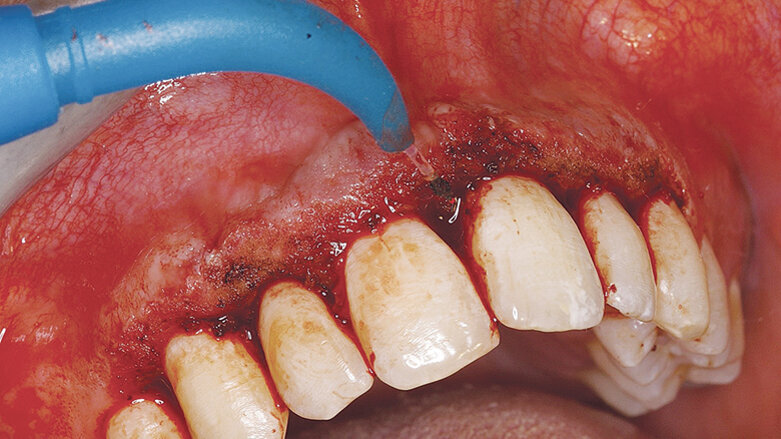

Odstraňování nežádoucích hyperplastických tkání pomocí diodového laseru AMD Picasso s jednorázovým hrotem.

Za účelem korekce tohoto konkrétního defektu jsme měli na výběr mezi skalpelem nebo laserem. Přiklonili jsme se k použití diodového laseru, který se snadno používá a nezpůsobuje krvácení v ráně, díky čemuž odpadá nutnost aplikace parodontálního obvazu, která by byla nutná k zakrytí výsledné rány po použití skalpelu.

Výsledků zdokumentovaných na obrázcích 1–4 bylo dosaženo pouze pomocí diodového laseru Picasso (AMD LASERS).